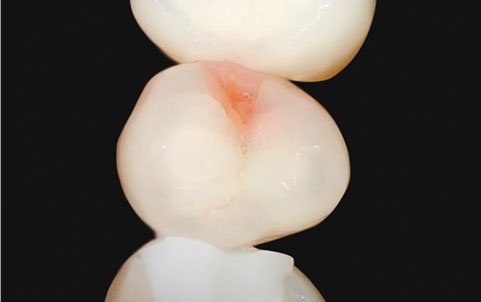

05

荧光分析, 用视频精密检查

Qraypen C

用荧光装备能确认, 在自然光下难以识别的

牙菌斑, 牙结石, 蛀牙, 牙齿裂纹等

可同时进行一般拍摄和光学拍摄, 比较牙齿的现状 .[ 诊断蛀牙装备 (Qraypen C) ]

医疗器械2等级-光合式蛀牙诊断装置,

使用与难以接触到的牙齿面拍摄 通过一次荧光拍摄能确认牙齿的裂纹, 腐蚀, 牙菌斑等

除了能提前确认外, 修复牙齿的后期管理, 矫正患者的

蛀牙及牙菌斑管理, 蛀牙检查,

预防蛀牙等都能确认并改善 .

一般拍摄

光学拍摄 -